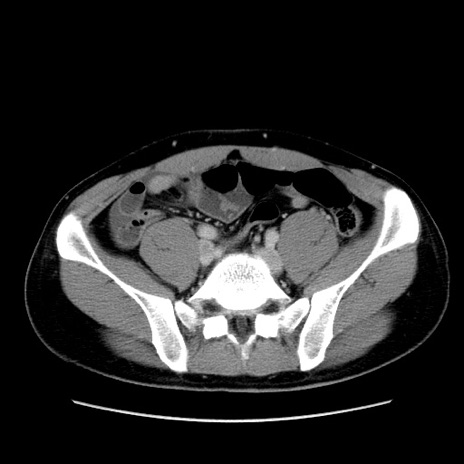

症例36(横断像)

【症例】20歳代 男性

【主訴】心窩部痛

【現病歴】今朝より上腹部痛あり。一旦軽快していたが再度出現したため救急要請。昨日夕に白身の魚を含む刺身を食べた。

【身体所見】BP 136/89mmHg、HR 74/min、BT 37.0℃、腹部:膨満、軟、心窩部に圧痛あり。反跳痛なし、筋性防御なし、腸雑音やや亢進あり。

【データ】WBC 17700、CRP 0.48